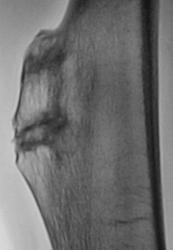

Девушка 21 года предъявляет жалобы по поводу болей в бедре, несколько проксимальнее коленного сустава, по латеральной поверхности ближе кпереди. Эти боли, в основном, имеют место быть, при ходьбе, и менее резкие - при сгибании ноги в коленном суставе. Длительное время проводится наблюдение, делаются рентгенограммы, консультирована в областном центре, НО специалисты не советуют "трогать".

Костно-хрящевой экзостоз, холмовидный. Диф. ДЗ с остеохондромой. У нас детей с такой патологией оперируют.

1.остеохондрома - синоним костно-хрящевой экзостоз, отдельно, отдельно, как опухоль и дисплазию их рассматривали до середины 70-х годов прошлого века.

2. выраженой динамики за 8 лет нет. Как правило, если нет заметного роста и образование не мешает жить, его оставляют под наблюдение.

3. сомнительно, что именно данное образование вызывает клинику, обычно - это случайная находка. Каким образом его выявили в этом случае? пальпируется ли оно? Возможно, проблема в коленном или т/бедренном суставе, не исключен вариант канцерофобии...

Уважаемый V1tal! вы безусловно правы, остеоходнрома озлокачествляется во вторичную хондросаркому и озлокачествляется как раз хрящевой компонент или "шапочка" экзостоза, одним из признаков малигнизации как раз является несоответствие больших размеров пальпируемой опухоли меньшим размерам ее на рентгенограмме, т.к. хрящевая "шапочка" не рентгенконтрастна.

Указаный Вами участок это не только зона склероза, но и обызвествление в зоне хрящевого компонента, оно может иметь нечеткие и неровные контуры. Тем не менее, отрицательной динамики с 2001 года я не вижу. Последние снимки очень хорошего качества, видны окружающие мягкие ткани, на мой взгляд их структура сохранена.